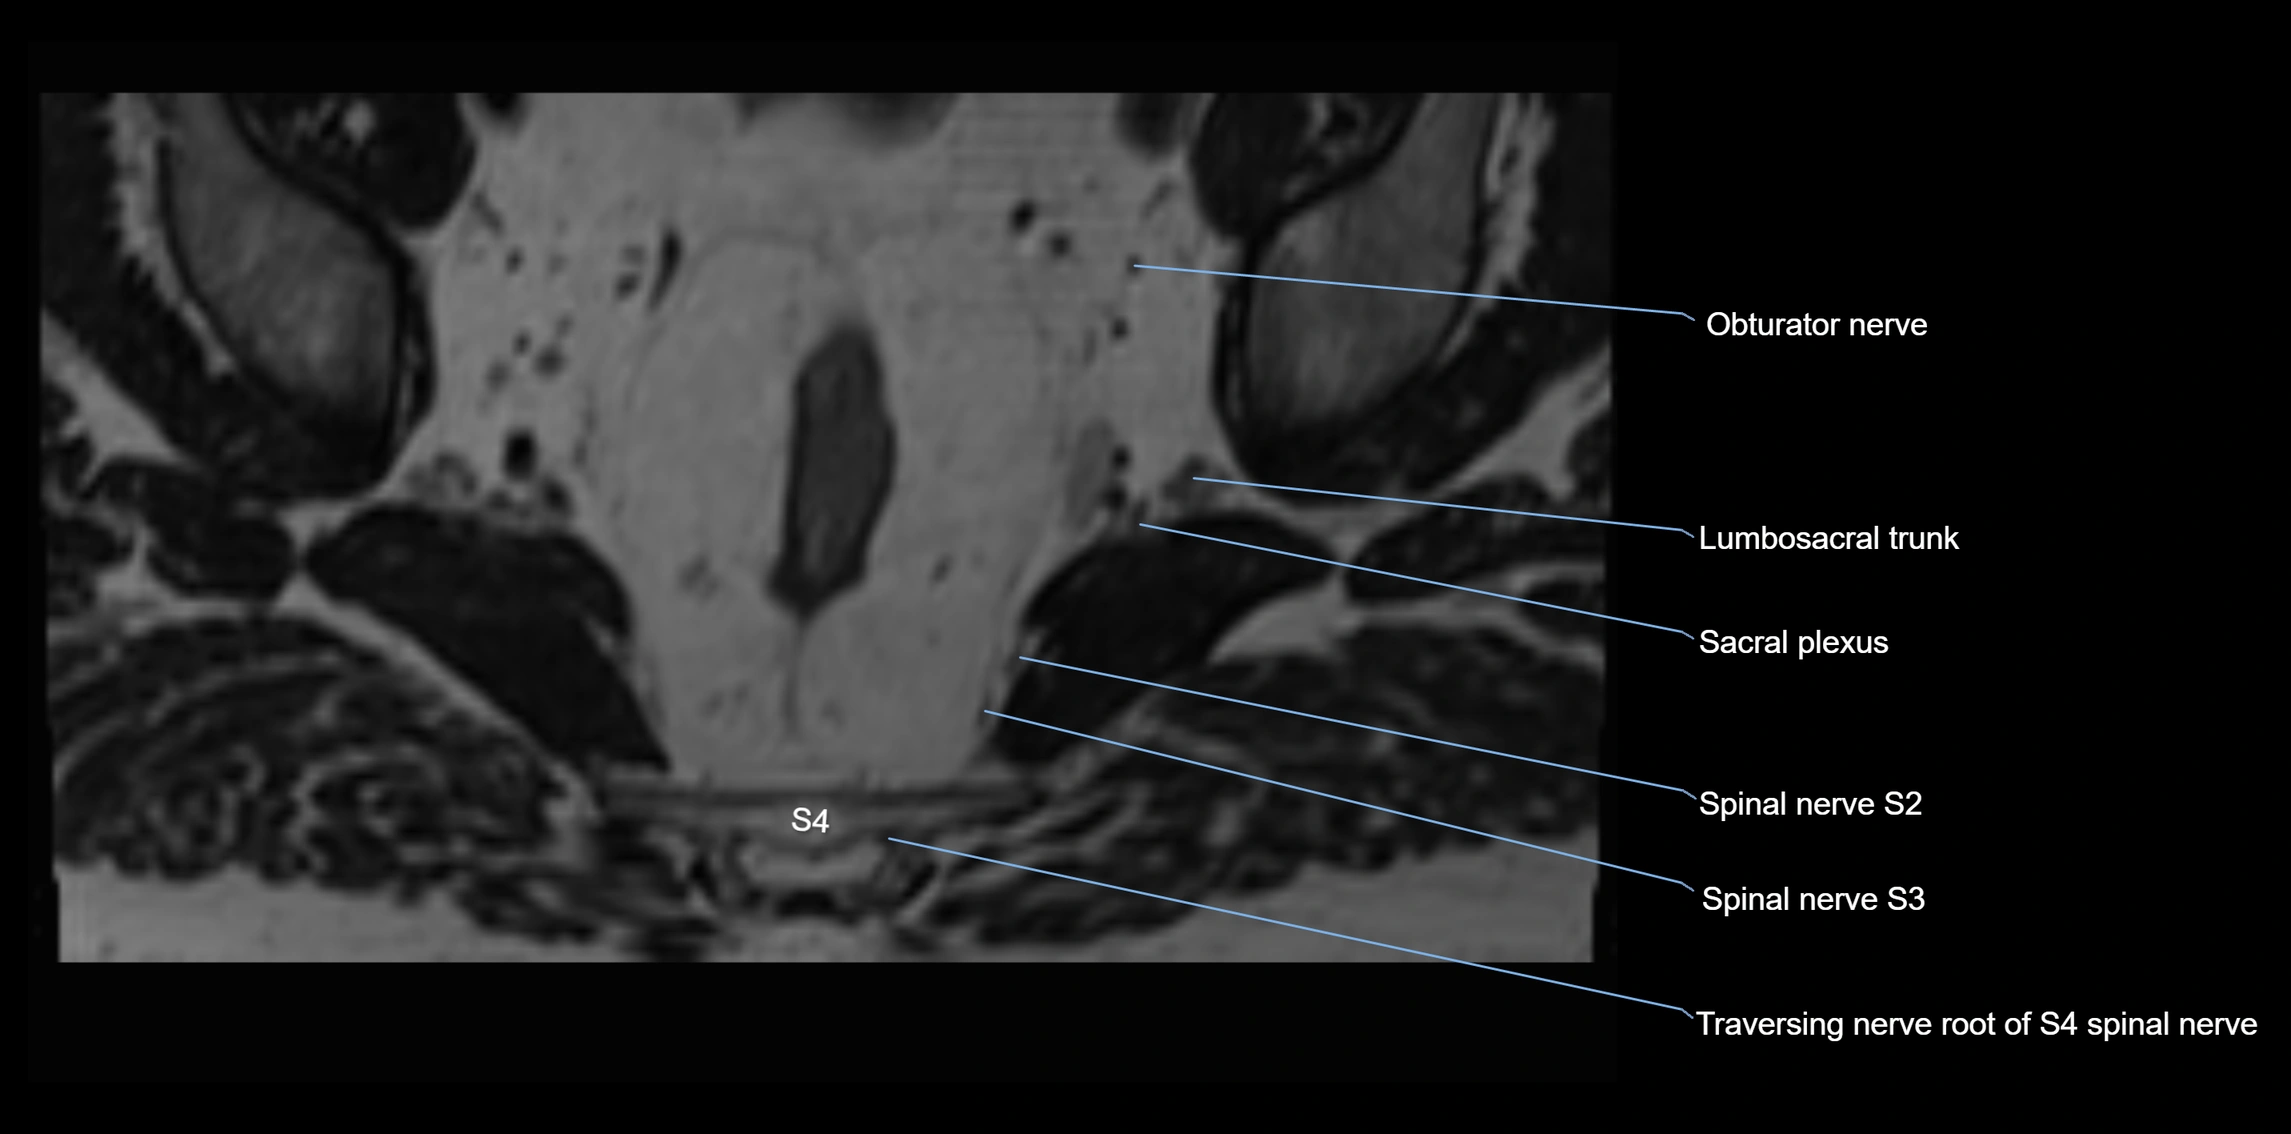

MRI image

image